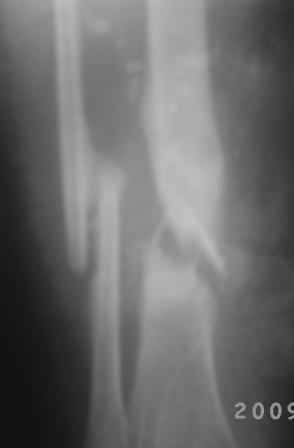

Посттравматический ложный сустав б/берцовой кости.

Добрый вечер, уважаемые коллеги! Обратилась женщина, 30 лет. ДТП 11 октября 2008 г. Из выписки: О/многооскольчатый перелом костей левой голени по Каплану 3В,

ПХО раны, гипсовая повязка, перевод в гор.б-цу, в 21.10.08г КДО аппаратом Илизарова(почему-то в вальгусном положении), ч-з два месяца тромбофлебит лев.н/конечности, отеки, воспаление, и аппарат сняли, с тех пор ходит в гипсовой повязке со стременем. к-рую периодически меняют, якобы кость со временем срастется.

На уровне н/з голени глубокие рубцы по передне-медиальной поверхности, умеренная отечность голени, незначительная патологическая подвижность, умерен. болезненность, ось правильная, укорочение 1,5см.

Наш план БИОС после остеоклазии м/берцовой кости. Но укорочение еще будет увеличиваться!

Как стратегический план - вполне приемлемо, но есть много тактических вопросов. И сохранение длины, и трудности с восстановлением оси, и канал сформировать нелегко будет, да еще и риск инфекции. Мы бы, наверно, сделали в два этапа - восстановление длины и оси аппаратом, потом гвоздь с цементным покрытием.